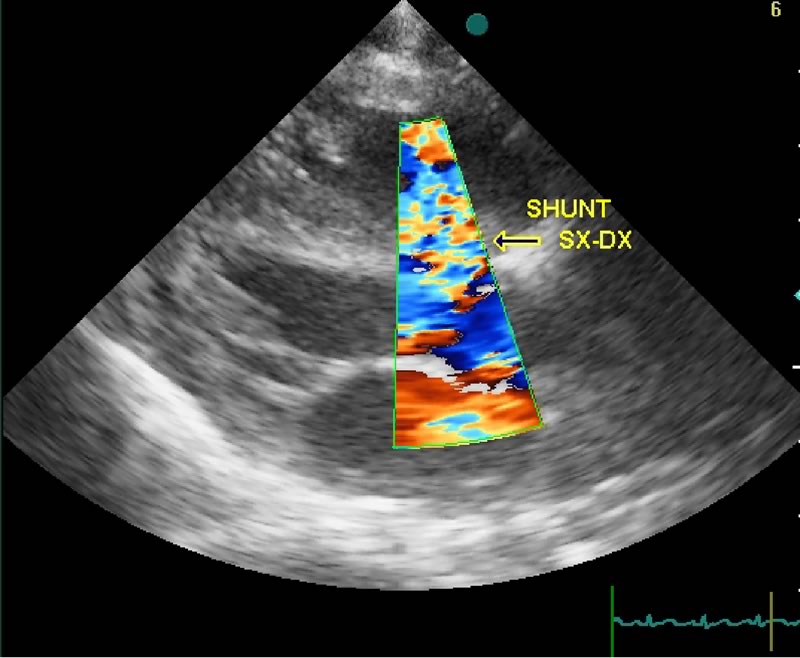

Al momento del ricovero il bambino è tuttavia polipnoico, con rientramenti al giugulo, epigastrici e intercostali, tosse stizzosa in decubito supino e presenta facile affaticabilità durante i pasti, epatomegalia. All'obiettività cardiologica appare un accenno di bozza precordiale, polsi molto ampi, itto e fremito epigastrico, soffio sistolico ad alta frequenza di intensità 3/6. La valutazione della Radiografia del torace (Fig. 1) evidenzia una cardiomegalia con ipertrofia biventricolare, senza chiari segni di iperaflusso polmonare. Evidente l'ipertrofia timica già descritta.